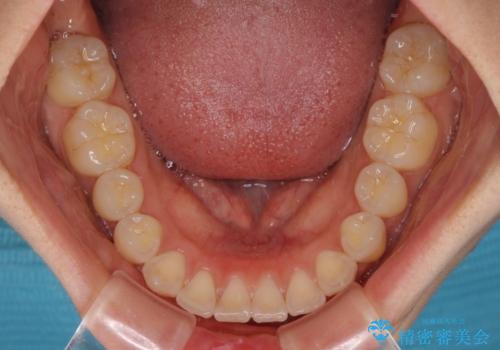

- 上下のデコボコと前歯のクロスバイトを改善したいとのことで来院された患者様です。

極力短期間で治療したいとのことで、ワイヤー装置による矯正治療を行うこととしました。